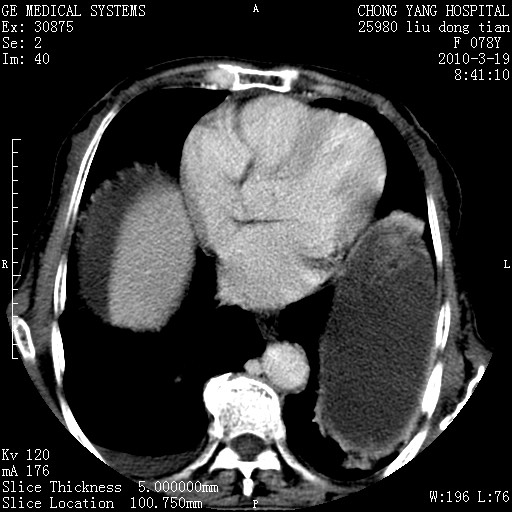

标题: CT25199:F 78Y 腹胀半年 消瘦乏力 [打印本页]

脾脏病灶无强化,像多发囊肿或淋巴管瘤,不除外淋巴瘤(低强化);

脾脏病灶像车轮 莲花,第一感觉还像包虫呢。真想全切出来一个个做病检。

考虑nhl,肝、脾、腹膜腔及腹膜后多发淋巴结受侵,腹水,右肾囊肿,慢性胆囊炎,右侧少量胸腔积液。

最后报的胰头癌多发转移,脾脏单独考虑囊肿或淋巴管瘤。